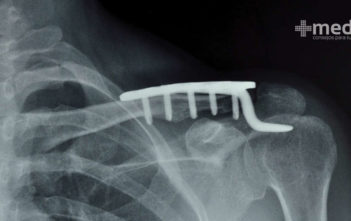

Cirugías de ortopedia más comunes Una cirugía de ortopedia es cualquier operación realizada en el…

Lesiones de huesos en el adulto mayor Cuando los tejidos del cuerpo sufren daño se…